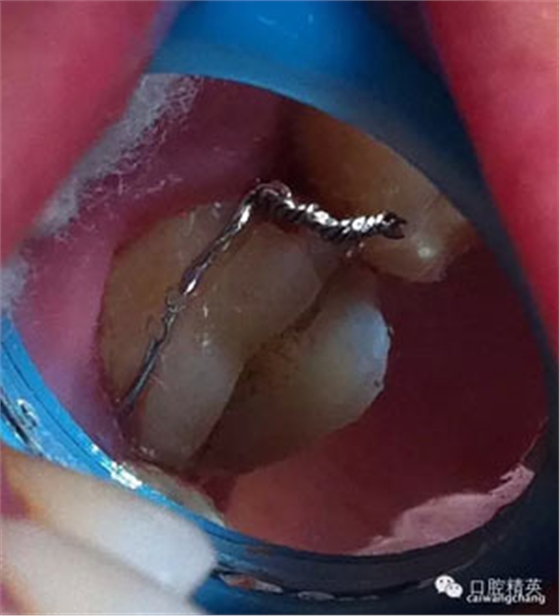

先給與根管充填(前提是無根管劈裂),牙膠截斷于根管口

頰部預備溝槽,準備結扎絲復位,現(xiàn)已改為成型夾或血管鉗鉗夾復位

復位后可見基本對齊